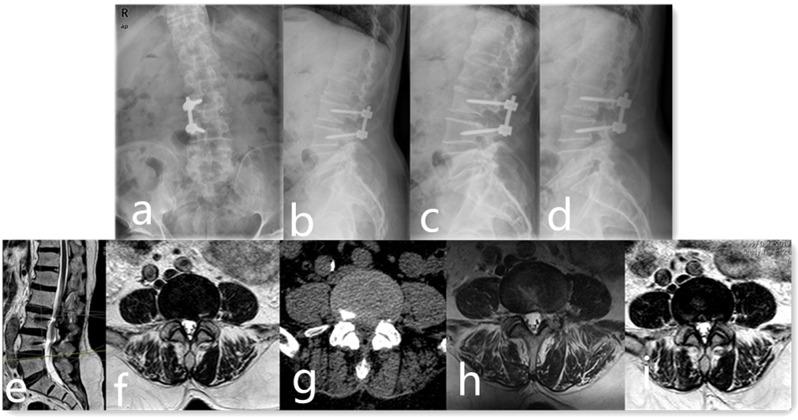

66 patients with symptomatic ASD who failed conservative treatment for more than 1 month and received repeated lumbar surgery were retrospectively collected in the study from January 2015 to November 2018, with the average age of 65.86 ± 11.04 years old. According to the type of surgery they received, all the patients were divided in 2 groups, including 32 patients replaced the prior rod in Group A and 34 patients received PELD at the adjacent level in Group B. Patients were followed up routinely and received clinical and radiological evaluation at 3, 6, 12 months and yearly postoperatively. Complications and hospital costs were recorded through chart reviews.

The majority of patients experienced positive surgical outcomes. However, three cases encountered complications. Notably, Group B patients demonstrated superior pain relief and improved postoperative functional scores throughout the follow-up period, alongside reduced hospital costs (P < 0.05). Additionally, significant reductions in average operative time, blood loss, and hospital stay were observed in Group B (P < 0.05). Notwithstanding these benefits, three patients in Group B experienced disc re-herniation and underwent subsequent revision surgeries.